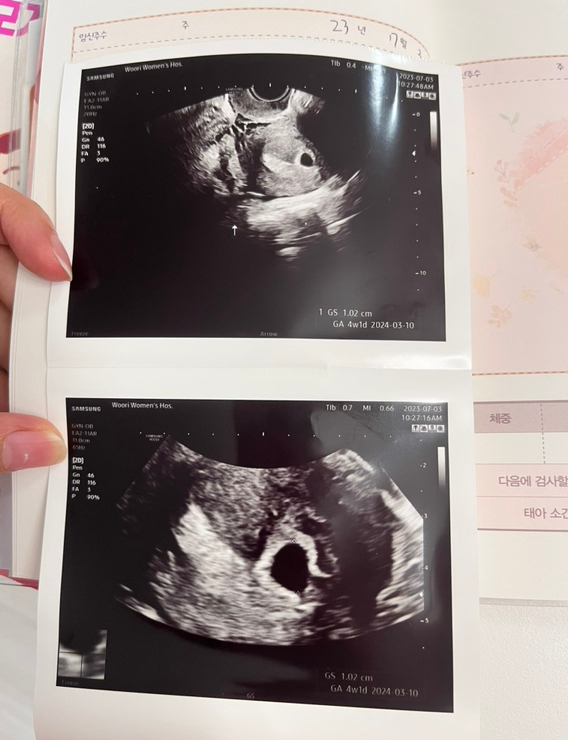

임신 5~9주 차 기록, 고통스러운 입덧과 초음파 기록

벌써 어느덧 저희 부부의 아기 해피가 9주 차 후반부에 접어들었답니다! 칼같이 4주 차부터 시작한 입덧… ...

임신 4주 차 임신 초기 증상과 태몽, 병원 선택 국민행복 바우처 신청과 태명 짓기

안녕하세요 여러분! 희주입니다. 오늘 포스팅은 저희 집 경사 소식이에요~ 제목만 봐도 알 수 있는... 임신...